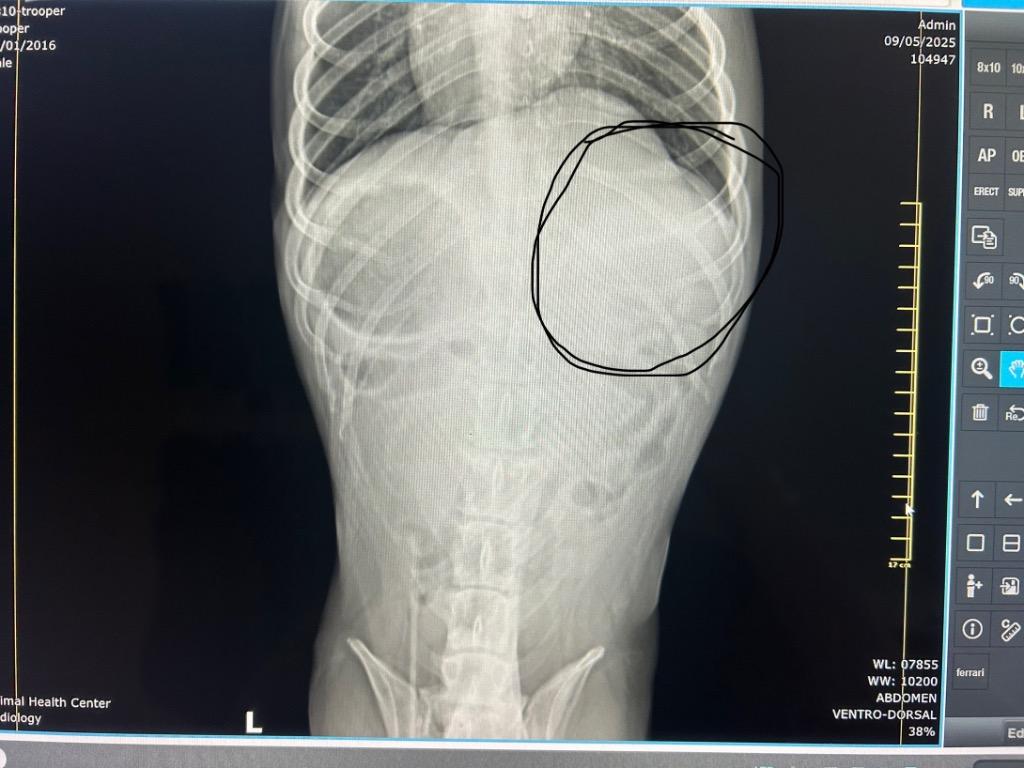

Typical lifespan: 11โ17 years ยท Breed: Pit Bull Mix / Staffordshire Terrier Mix

Computer vision estimates 8โ11 years (high confidence).